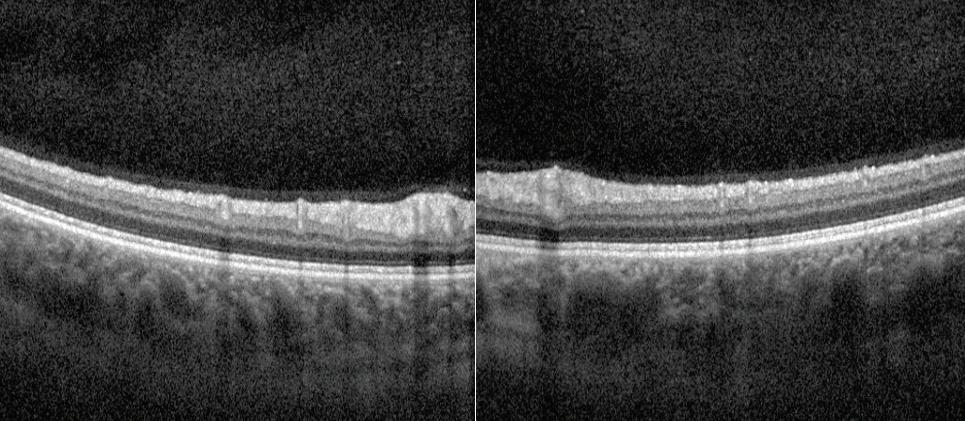

Ocular dialysis disequilibrium describes a proposed phenomenon whereby intraocular pressure increases during hemodialysis due to disproportionate changes in the osmolality of aqueous humor as opposed to the blood. This imbalance in osmolality is thought to disrupt the equilibrium between production and outflow of aqueous humor in the eye, which determines the intraocular pressure (IOP) (1). Elevations in intraocular pressure can lead to visionthreatening complications such as acute angle closure glaucoma, both in patients with existing glaucoma and those without. Furthermore, other risk factors or acute conditions can contribute to IOP elevations and may also need to be controlled. In the case presented below, a pars plana vitrectomy (PPV) and intraocular lens (IOL) exchange complicated by hyphema and vitreous hemorrhage likely exacerbated the issue,

as both can lead to increased ocular inflammation with blockage of the trabecular meshwork. This case presents an interesting etiology and potential solution for intraocular pressure elevation in an end-stage renal disease (ESRD) patient undergoing hemodialysis.

Case Presentation

A 74-year-old male presented for partially dislocated posterior chamber intraocular lens (PCIOL) in his left eye, which was his only functional eye. He suffered from multiple chronic illnesses, including Merkel cell carcinoma of the right eyelid and right parotid gland (currently in remission), blindness of the right eye due to complications from radiation treatments, chronic obstructive pulmonary disease, atrial fibrillation, gastroesophageal reflux disease, obstructive sleep apnea, coronary artery disease, and ESRD treated with dialysis for several years. Of note, the patient had not had any previous glaucoma or ocular hypertension issues. He subsequently underwent uncomplicated pars plana vitrectomy with IOL exchange with a scleral sutured IOL in the left eye. One day postoperatively the patient had a visual acuity of 20/40, but by day 3 post-operation, his vision had declined. One week post-operation, the patient’s vision was restricted to perception of hand motion only (HMO) with severe pain, and significant vitreous hemorrhage, hyphema, and small nasal choroidal effusion noted on examination. His measured intraocular pressure was 39 mmHg, far exceeding the generally accepted “normal” range of 10 to 21 mmHg. We were able to regain control of the IOP with administration of topical brimonidine, dorzolamide, timolol, Xalatan®, and oral Diamox®. With the patient’s IOP acutely managed, the plan at that time was to observe in the outpatient setting for spontaneous resolution of the previously noted hyphema and vitreous hemorrhage. However, during this observational period, he returned several times for urgent appointments due to severe pain,

in addition to nausea and vomiting. At this time, he was noted to have severe IOP elevations, with maximum recorded IOP reaching 53 mmHg. Given the unclear etiology of the patient’s symptoms, he was admitted to the hospital for pain control and very close observation. Over the course of his inpatient stay, his IOP was checked frequently and noted to only severely spike in the evenings after dialysis. He was evaluated multiple times while on dialysis and never had significant elevation of IOP during treatment itself. At that time, we surmised that fluid shifts were a possible etiology of his symptoms, especially with vitreous humor now absent post PPV. Lengthy discussions with nephrology led to a plan to prolong dialysis treatment times, running the dialysis machine as slowly as possible to hopefully slow electrolyte and fluid shifts into the eye, with the goal of stopping the IOP spikes following dialysis sessions. The patient responded very well to this modified, prolonged dialysis protocol. His IOP never exceeded 24 mmHg and was typically in the middle to upper teens. Furthermore, with the addition of a fourth dialysis day per week, his IOP has been in the middle teens, even with discontinuation of Diamox. We have observed consistent IOP maintenance for months on this regimen. The patient additionally underwent anterior and posterior chamber wash out to treat his persistent vitreous hemorrhage. He is currently doing very well and seeing well from the previously affected eye. He has not had any significant IOP elevations since the alteration of his dialysis protocol.

Discussion

This case provides further evidence for the effect of hemodialysis on IOP, as well as a potential solution for managing IOP increases associated with said treatment. As mentioned above, one of the primary factors thought to contribute to changes in IOP is the changes in fluid osmolarity inherent to dialysis itself. Specifically, as molecules such as urea are removed from the blood, the osmolality of fluids in the body decreases. However, the decrease in aqueous humor osmolality is thought to be disproportional to the decrease in plasma osmolality, thus leading to hypertonicity of the aqueous humor. This hypertonicity leads water to move into the aqueous space (1). Additionally, a population-based study conducted in Malaysia found that the presence of chronic kidney disease may itself be another risk factor for elevated IOP due to impaired aqueous outflow (2).

Regarding management of IOP elevations during dialysis, the available body of literature is somewhat limited. While several possible solutions have been reported in prior studies, there does not appear to be a widely used protocol at this time. Prior suggested solutions have included administration of intravenous glucose, pan-retinal photocoagulation for neovascular glaucoma, and surgical interventions such as Ahmed valve implantation (1, 3–5). A case report by Maja et al. did note an attempt at decreasing dialysis rate as an intervention but ultimately resorted to placement of an Ahmed valve when dialysis modification was ineffective (3).